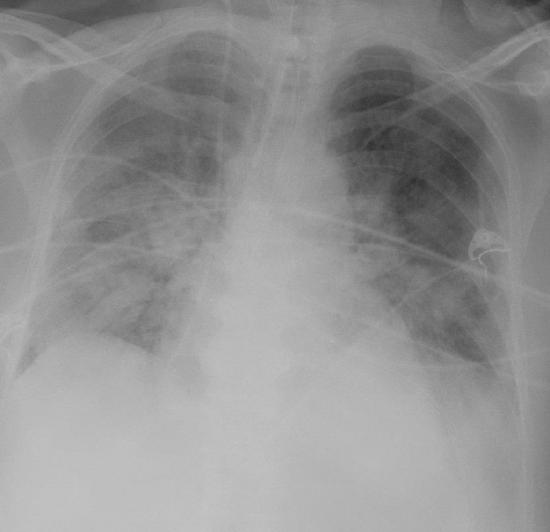

Figure 5.7: Diffuse bilateral densities associated with ARDS.

Radiographic findings are an essential part of diagnosing the ARDS patient and will show diffuse bilateral interstitial and airspace densities caused by the edema (figure 5.7). Normal heart and vessel size and absence of pleural effusion distinguish ARDS from cardiogenic pulmonary edema. Although the x-ray gives the appearance of diffuse edema, high-resolution CT often shows that the process is heterogeneous and patchy. This heterogeneity is reflected by remnant patchy fibrosis if the patient recovers; however, the mortality rate for ARDS is around 50 percent.